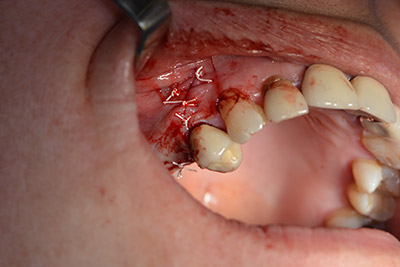

An absorbable membrane was used as the barrier in the buccal direction and covered the augmentation. Finally, saliva-proof sutures were placed (Fig. 15 to 19).

Augmentation with autologous bone

Image 15

Image 16